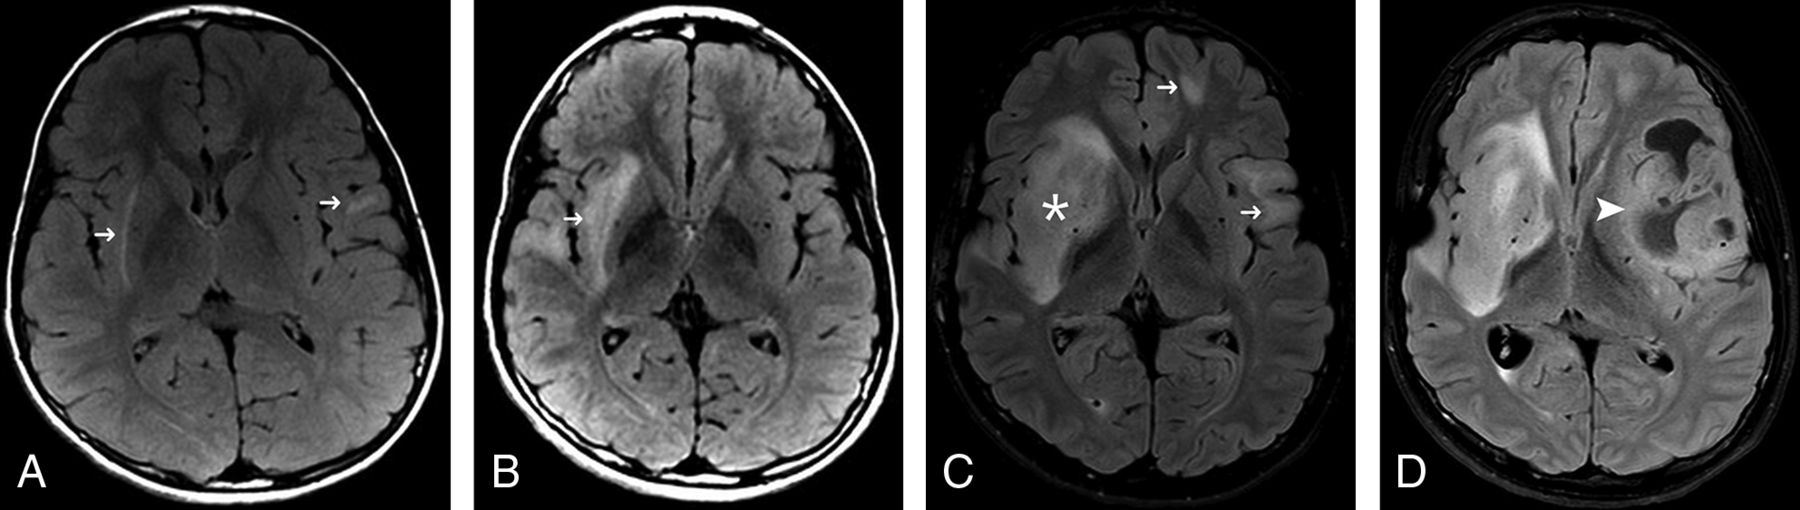

Twelve of the 14 patients (86%) presented with a network of prominent medullary veins converging into a single draining vein (caput medusae), meeting the conventional MR imaging criteria of developmental venous anomaly (DVA). These DVAs drained into the dural sinuses or ependymal veins. The average number of DVAs in patients who had them was 2.5 (range, 1–5). These DVAs were already present at the initial diagnostic imaging evaluation. DVAs were either supra- (mostly frontoparietal) or infratentorial (cerebellum and pons) or in both locations. No spatial association was found between DVAs and other parenchymal abnormalities (overt brain tumors, subcortical T2/T2-FLAIR hyperintensities) (Fig 5). These findings were seen on initial imaging with no new DVAs identified during follow-up.

Left cerebellar developmental venous anomaly seen in patient 1, as shown by axial SWI (A) and postcontrast T1 imaging (B).

Popcorn-like nonenhancing lesions with prominent T2*/SWI blooming artifacts suggestive of cavernous hemangiomas were identified in 3 of 14 patients (21%). These findings were seen on initial imaging with no new nontherapy-induced cavernomas identified during follow-up. After radiation therapy, several patients showed multiple foci of microhemorrhage, yet these were not considered to be primary cavernous hemangiomas. Not all patients had T2* or SWI sequences included in the MR imaging protocol.

Four patients showed nonenhancing T2/T2-FLAIR hyperintense white matter lesions within the supratentorial deep gray matter nuclei (globus pallidus and thalamus), similar to patchy T2/T2-FLAIR hyperintensities commonly seen in neurofibromatosis type 1 (Fig 6). All 4 patients were younger than 15 years of age. All lesions persisted during follow-up.

T2-weighted image of a diffuse astrocytoma in the left frontal lobe (asterisk) of a 14-year-old girl (patient 5). Ovoid nonenhancing hyperintense foci are noted in the right thalamus (arrow) and left globus pallidus, similar to focal areas of signal intensities commonly seen in patients with neurofibromatosis type 1.

Additional non-neoplastic brain MR imaging findings in CMMRD include DVAs and nontherapy-induced cavernous hemangiomas, as have been recently reported.20,21 Remarkably, 12 of our 14 patients had DVAs (typically multiple DVAs), indicating a considerably higher prevalence than that reported in healthy populations (6%–7%).22 Because DVAs are considered a normal variant, under-reporting is probably common. However, patients with primary brain tumors have a higher prevalence of DVAs than the healthy population (10.2% versus 5.3%, respectively).23 In our series of children with brain tumors and CMMRD, there was no apparent association between the tumor location and the location of the DVA. DVAs have a well-recognized association with cavernomas,24 which was also noted in some of our patients. The pathogenesis of these vascular anomalies is not clearly understood. DVAs might arise as a response to compromise of the normal venous drainage by stenosis, thrombosis, or maldevelopment. Cavernomas might occur in both sporadic and familial forms. Patients with familial cavernomas typically have multiple malformations. Familial cavernomas have been linked to 3 specific cerebral cavernous malformation genes KRIT1/CCM1 (Krev interaction trapped 1), MGC4607/CCM2 (cerebral cavernous malformation 2), or PDCD10/CCM3 (programmed cell death protein 10). Almost 80% of patients with the hereditary form have a heterozygous germline mutation in 1 of these 3 genes. Development of sporadic cavernomas is thought to be secondary to microhemorrhages and angiogenic growth factor activation in a cause-and-effect relationship with adjacent DVA.23,25,26 Recognizing vascular abnormalities in the brain, particularly DVAs, is important; hence, they seem to contribute to a potentially suggestive “imaging gestalt” in children with CMMRD.